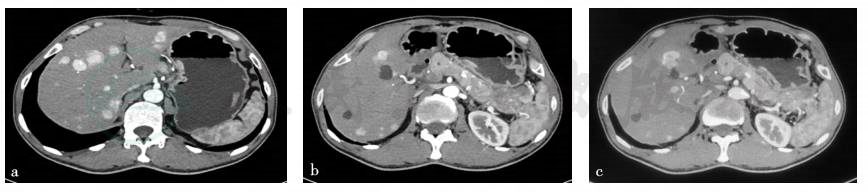

2017年4月12日全腹部CT平扫+增强:①胃窦部改变,考虑胃窦癌,建议进一步检查;②考虑肝内多发转移瘤,胰尾部转移瘤;③肝多发囊肿;④右肾多发囊肿;⑤腹腔少许积液(图2)。

图2 全腹部CT平扫+增强诊断